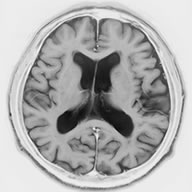

中でもSPECTとPETは体内の薬物の分布を3次元的に表示することができる検査で、SPECTは1方向、PETは2方向に放射線を出す放射線物質を用いる検査です。認知症、癌や内分泌の診断などに広く使用されています。

SPECT 認知症(アルツハイマー病)